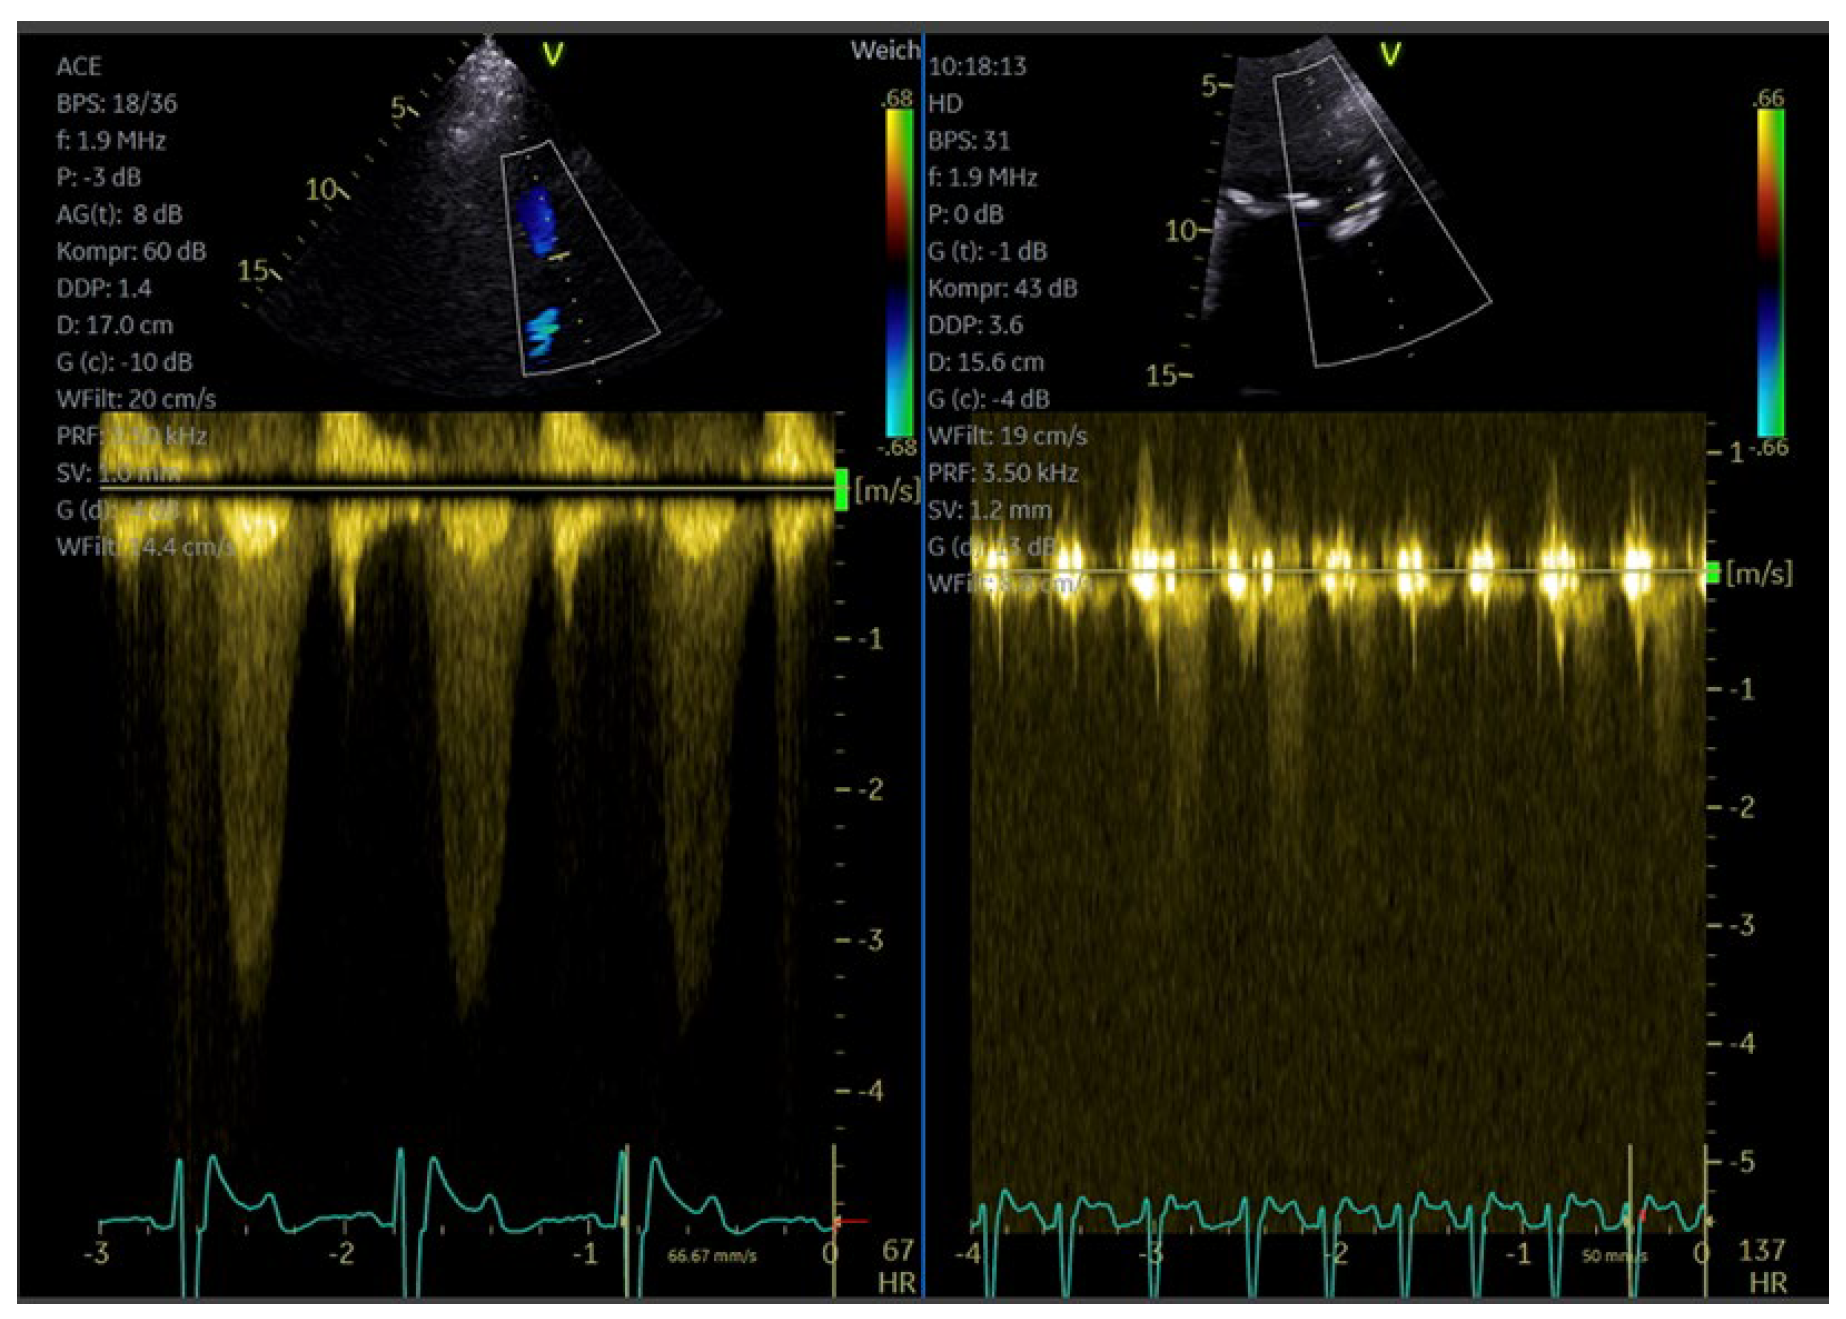

6. Enhancement of Doppler Signals

6.1. Background and Indications

6.2. How to Measure LAD Coronary Flow Velocity

6.3. Preparation and Performance for Enhancement of Valvular Flows

Technical Aspects, Settings

6.4. Velocity Measurements on Enhanced Doppler Recordings

| Imaging method | CW Doppler for aortic stenosis/tricuspid regurgitation PW-Doppler: for pulmonary–venous flow |

| Imaging planes | Same as for non-contrast Doppler imaging, the enhanced color Doppler signals facilitate the alignment of the cursor for spectral Doppler measurements |

| Contrast application | Bolus injection, the recordings can be performed during the washout after recordings for assessment of LV function |

| Typical findings | Intensive Doppler spectra Consider reduction in gain or power. |